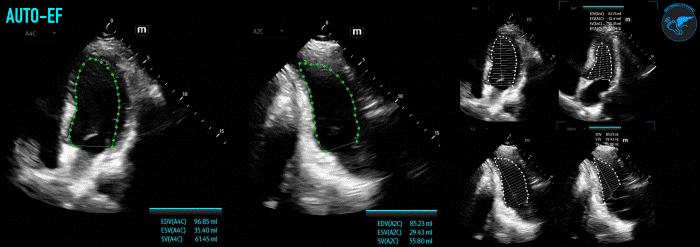

Newer ultrasound machines may now also come with integrated auto-intelligence (AI) package functions that can assist in determining LVEF (Figure 6). Although these AI tools are enticing to use due to their ease of use and rapid results, it is important to first understand the basics on performance of these measurements to identify any inconsistencies or errors the machine may be making.

LVSF_Figure 6_AutoEF v1.gifFigure 6. Example of AutoEF Plus Smart Tool on Mindray TE X Ultrasound System.